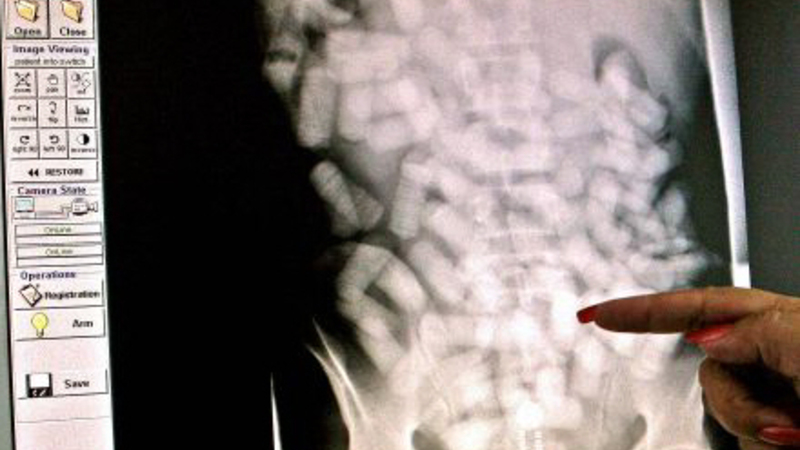

Det er tydeligt at se poserne med narko på scanningsbilleder

I alt er 21 narkosmuglere fanget i år med kokain eller heroin i mavesæk eller endetarm i Københavns Lufthavn. Det er syv gange så mange som sidste år, hvor tolderne kun fangede tre smuglere med narko i kroppen, viser nye tal fra Københavns Politi. Derudover blev blandt andet en mandlig smugler anholdt i Billund Lufthavn i juli måned efter at have smuglet et kilo kokain i maven fra Spanien.

De sluger fra 500 gram og op til et kilo narko, mens én mand er taget med hele 1,233 kilo narko i organerne. Typisk smugles kokain, men også heroin finder vej til danske misbrugere i smuglernes maver.